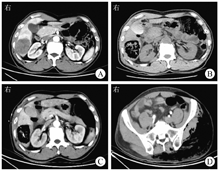

患者男,60岁,因"上腹部疼痛1 d"于2022年6月30日收入盐城市第三人民医院。患者5个月前因"右上腹疼痛1周"在盐城市第三人民医院诊断为"肝脓肿(大肠埃希菌感染)、迟缓埃特菌菌血症"并行肝脓肿引流术,同时发现"升结肠管壁稍增厚,周围渗出",查癌胚抗原为3.10 μg/L,糖类抗原72-4为2.89 U/mL,白细胞计数为15.14×109/L,中性粒细胞计数为14.48×109/L。予抗感染、抗炎、肝素抗凝、足量补液等对症治疗,患者症状好转出院。其余既往史无特殊。患者1 d前无明显诱因出现右上腹部持续性胀痛,无畏寒、发热、恶心、呕吐,就诊于江苏省盐城市第三人民医院。入院体格检查:体温为36.2 ℃,脉搏为116次/min,呼吸频率为18次/min,血压为102/68 mmHg(1 mmHg=0.133 kPa);神志清楚,痛苦面容,皮肤、巩膜黄染,无出血点及皮疹,无肝掌、蜘蛛痣,全身浅表淋巴结未触及肿大;颈软,无抵抗;心、肺未见异常;腹软,右上腹压痛,无反跳痛、肌紧张,墨菲征阴性,肝脾肋下未触及,腹部无包块,移动性浊音阴性。双侧巴宾斯基征阴性。6月29日急诊查上腹部CT示肝右后叶下段占位,肿瘤待排;肝囊肿;结肠肝曲管壁增厚且灶周淋巴结肿大,结肠肿瘤待排(图1A)。入院当天查白细胞计数为2.28×109/L,中性粒细胞计数为2.14×109/L,血红蛋白为80.0 g/L,血小板计数为107×109/L,超敏CRP为229.54 mg/L,降钙素原为18.59 μg/L,纤维蛋白原为5.08 g/L,血肌酐为136.4 μmol/L,血尿素氮为9.03 mmol/L,随机血糖为7.5 mmol/L,总胆红素为10.1 μmol/L。

为明确肝脓肿病因,于入院当天急诊行肝脓肿穿刺术,复查上腹部CT示肝脓肿并产气进展(图1B)。继续予注射用头孢吡肟(2.0 g,每12 h 1次)静脉滴注,替硝唑氯化钠注射液(200 mL,每天1次)静脉滴注治疗。入院第2天,患者出现左髋部红肿热痛,复查CT示肝脓肿穿刺引流中,左侧臀部、盆部、肌群多发积气,升结肠管壁增厚,周围渗出,腹盆腔少量积液(图1C、图1D)。入院第2天查白细胞计数为5.18×109/L,血红蛋白为75.0 g/L,血小板计数为113×109/L,超敏CRP为229.98 mg/L,纤维蛋白原为6.39 g/L,血肌酐为195.9 μmol/L,血尿素氮为11.47 mmol/L,肌红蛋白>2 000 μg/L,肌酸激酶>12 800 U/L,总胆红素为46.1 μmol/L,癌胚抗原为7.98 μg/L,糖类抗原72-4为8.67 U/mL。考虑产气荚膜梭菌感染可能,给予亚胺培南西司他丁钠(1.0 g,每8 h 1次)静脉滴注、利奈唑胺(0.6 g,每12 h 1次)静脉滴注抗感染等治疗。